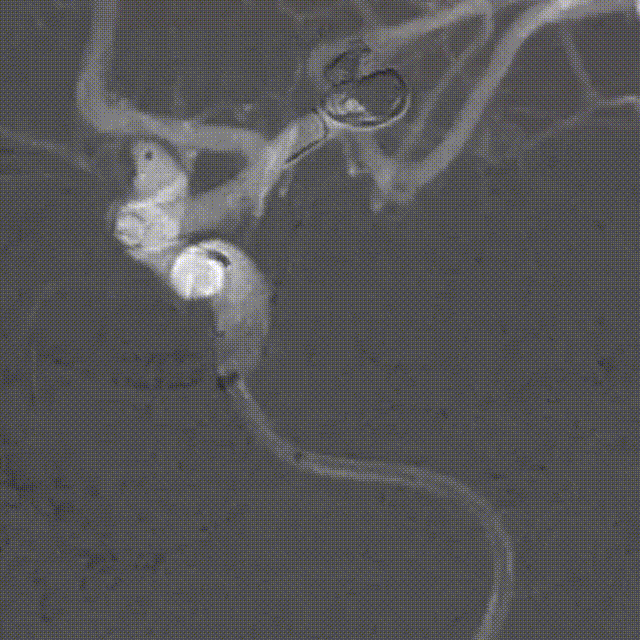

入院后DSA:左侧颈内动脉眼动脉段前壁动脉瘤;大脑中动脉瘤支架辅助栓塞术后表现。

颅内多发动脉瘤(左侧颈内动脉眼动脉段前壁动脉瘤;左侧大脑中动脉瘤栓塞术后)。

左侧颈内动脉眼动脉段前壁动脉瘤偏大,常规支架+弹簧圈治疗复发率较高,选择血流导向装置是更好的选择。